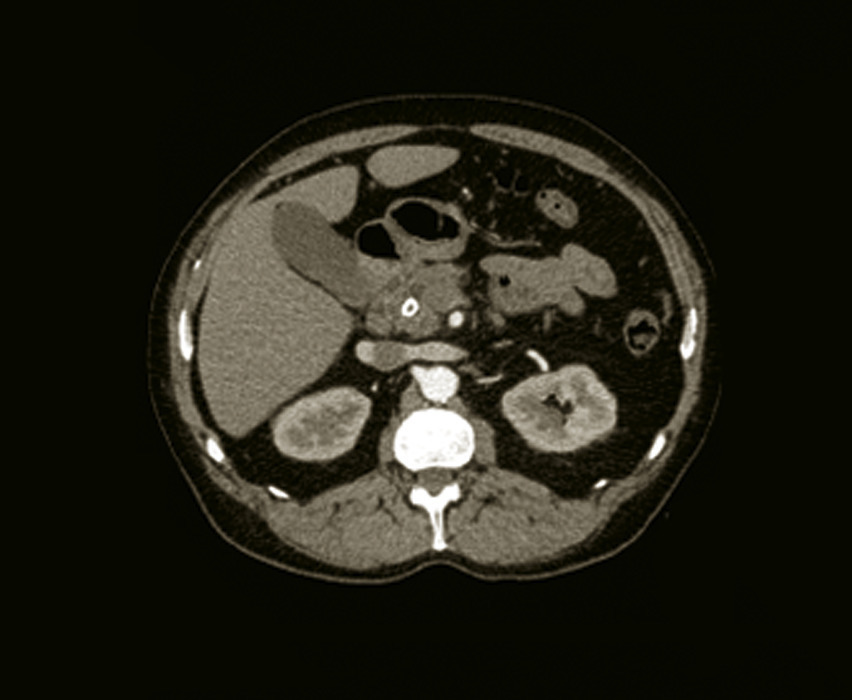

TDM abdominale sans et avec injection de produit de contraste : examen de référence (+++) ;

– meilleure description des lésions (calcifications diffuses ou focales, atrophie, calcul [fig. 2] + dilatation du canal de Wirsung en amont), de l’inflammation pancréatique (coulées de nécrose si poussée), d’éventuelles complications (pseudokyste, dilatation de la voie biliaire principale, hypertension portale segmentaire).